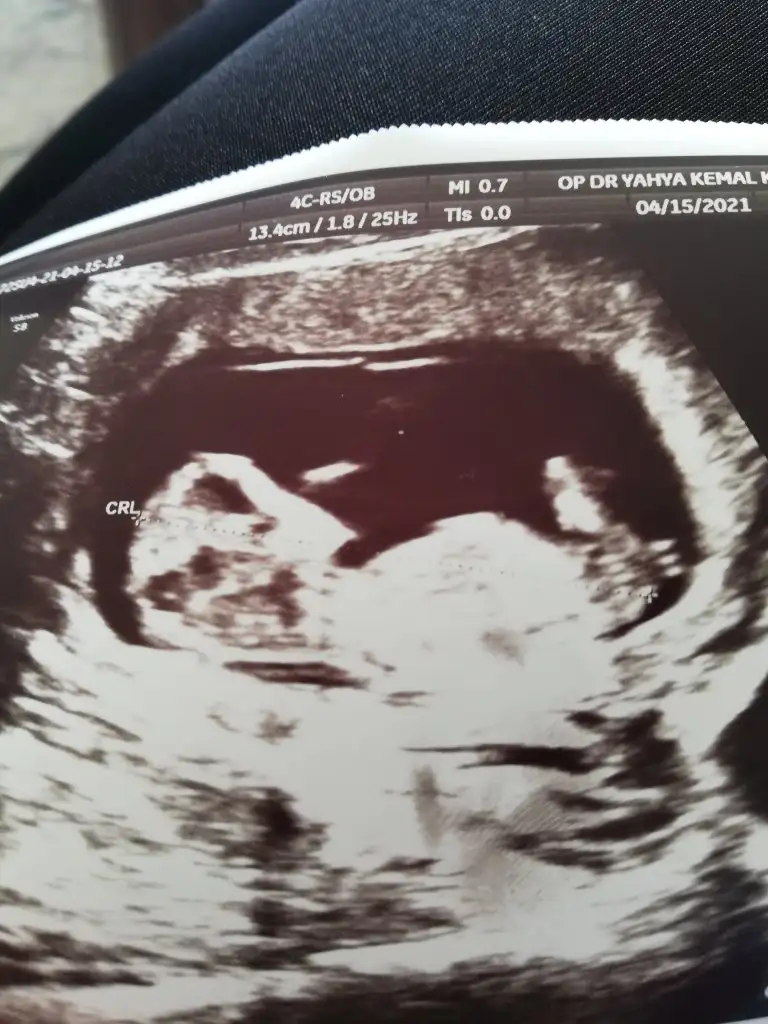

Tekrar USG paylaşın demiştiniz 12+5 günlük burada doktor bir tahmin yapmadı ne düşünüyorsunuz :)Ikra meyra

Kız görünüyorIkra meyra bana 11 haftalikken kız demiştiniz. Şimdi 12 haftalik kontrolden geldim. Doktor bacak arasini da çekti ama hiç tahminde bulunmadı. Sizce hala kız mı?